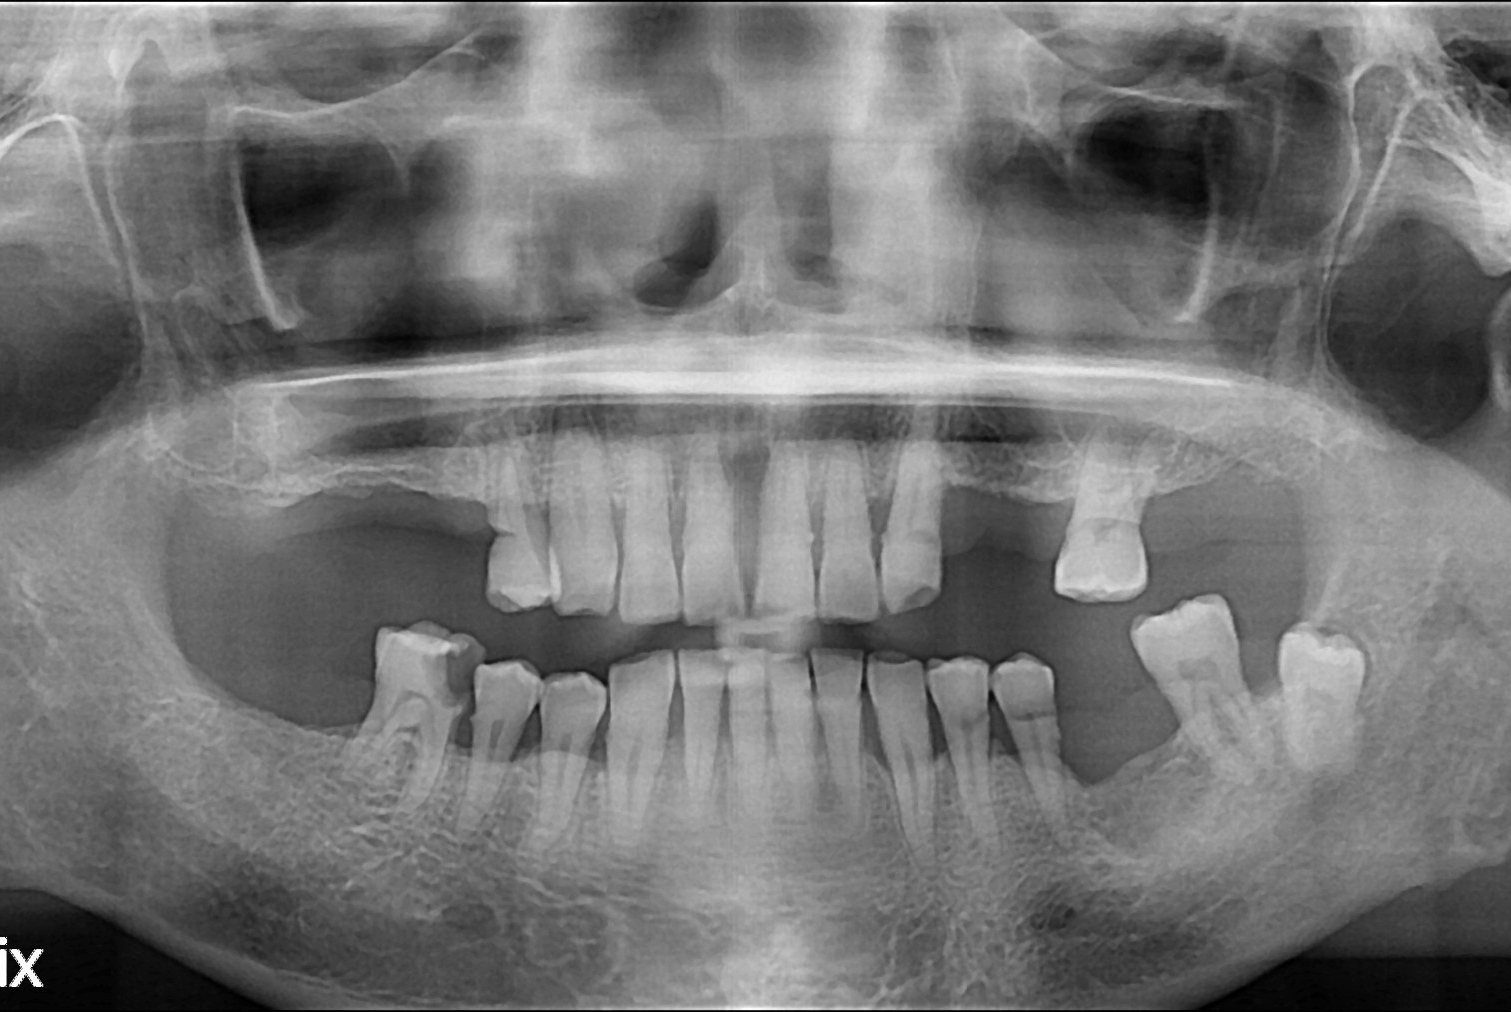

치료전 : 2018-10-26

세종치과는 많은 환자와 다양한 케이스를 바탕으로 항상 편안한 임플란트 수술을 제공하고자 노력하고,

오래동안 튼튼히 쓸 수 있는 임플란트 수술을 가장 큰 목표로 삼고 있습니다